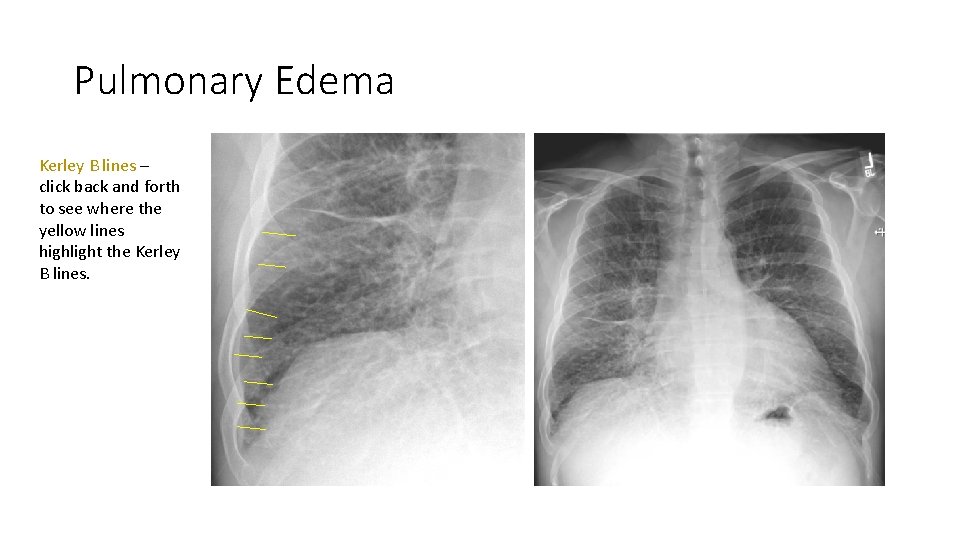

Pulmonary Edema Kerley B lines – click back and forth to see where the yellow lines highlight the Kerley B lines.